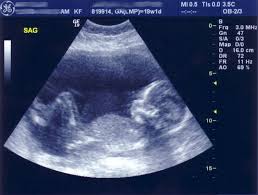

حذرت نتائج دراسة أجراها فريق من الباحثين الأمريكيين، من تعرض الأم الحامل خلال الثلاثة أشهر الأولى من الحمل لأشعة الموجات فوق الصوتية، الأمر الذي يعرض الجنين للإصابة بمرض التوحد.

وتوصلت الدراسة التي أجريت على أكثر من 2600 أسرة، أن تعرض الحامل لأشعة الموجات فوق الصوتية، خلال هذه الفترة يزيد من حدة الاضطرابات المرتبطة بمرض التوحد لدى الأطفال المعرضون جينيا للإصابة به.

وأكد الباحثون على عدم وجود مخاوف من التعرض لهذه الأشعة في الربع الثاني والثالث من الحمل.

جدير بالذكر أن الباحثون أجروا فيما سبق، أبحاثهم على الفئران الذين تعرضوا لهذه الموجات فوق الصوتية، مما يجعل السلطات الطبية تحذر من التقاط صورا تذكارية للأجنة فيِ بطِون أمهاتهم.